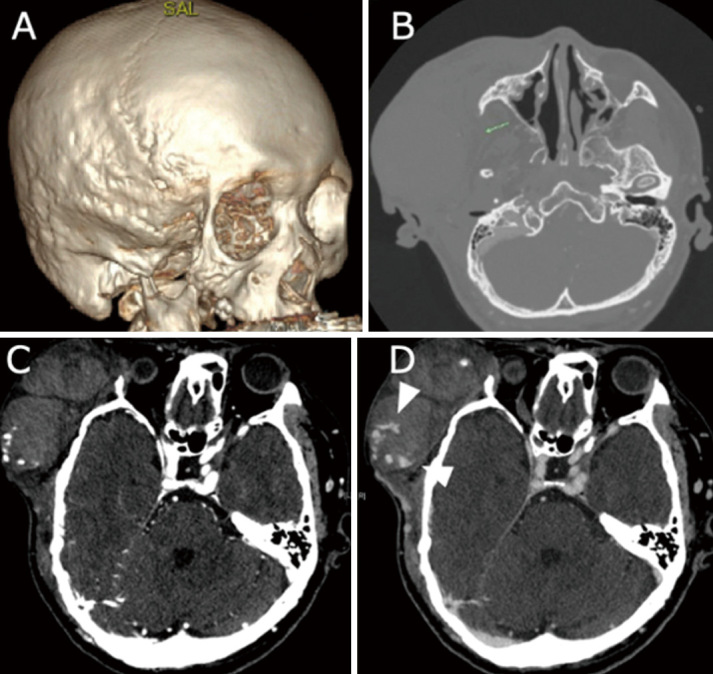

Patients with neurofibromatosis type 1 not only have characteristic skin findings but are also known to have vascular disorders due to vascular vulnerability. A 44-year-old man with previously undiagnosed neurofibromatosis type 1 was brought to the emergency room due to a sudden subcutaneous hematoma with no history of trauma. Angiography revealed extravasation from the parietal branch of the right superficial temporal artery, which was embolized with n-butyl-2-cyanoacrylate. However, the next day, the patient exhibited an increased subcutaneous hematoma, and new extravascular leakage was detected at the frontal branch of the superficial temporal artery, which was also embolized with n-butyl-2-cyanoacrylate. The patient had physical findings characteristic of neurofibromatosis type 1, such as café-au-lait spots, and was subsequently diagnosed with neurofibromatosis type 1. No obvious neurofibroma or any other subcutaneous lesion associated with neurofibromatosis type 1 was identified in the affected area. Massive idiopathic arterial bleeding in the scalp, although infrequent, can be fatal. Neurofibromatosis type 1 should be considered when a subcutaneous scalp hematoma is observed without a history of trauma, even if the facial skin structure appears normal. Neurofibromatosis type 1 is also known to have multiple sources of hemorrhage. Thus, it is important to repeatedly evaluate vascular structures via cerebral angiography, contrast-enhanced computed tomography, and magnetic resonance imaging, if necessary.